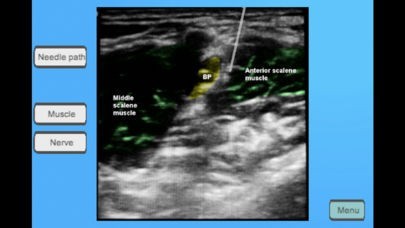

Regional Anesthesia Assistant for iPhoneのスクリーンショット

App Storeより引用This app is designed as a quick reference tool to be used by practicing anesthesiologists or anesthesiology residents who are performing regional anesthesia. It includes suggestions for ultrasound machine and probe placement, needle insertion site/angle, as well as anatomical ultrasound picture with surrounding structures. This app is best used as a warm up tool and should not be considered a comprehensive review of materials. What is presented in the app is based on our own clinical experiences and not medical evidence. We hope you enjoy!